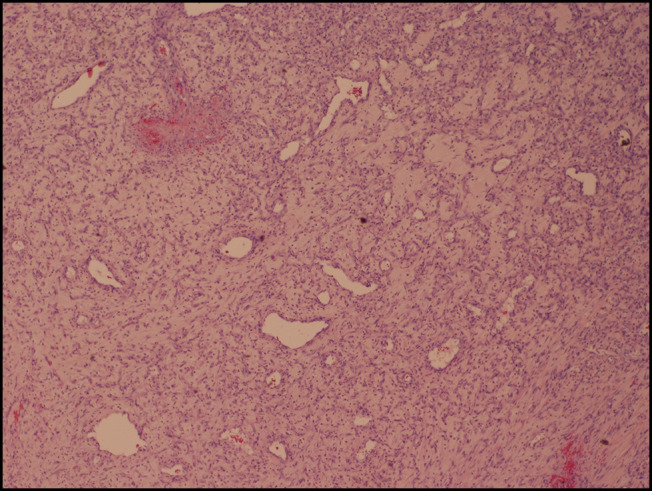

化脓性肉芽肿是一种良性血管病变,常见于皮肤和粘膜,但很少发生在胃肠道。本病例突出显示小肠内的大PG,引起慢性贫血,并作为肠套叠的先导点。我们讨论其诊断挑战,潜在的误诊,和治疗方案。本病例强调了临床医生对pg非典型表现的认识的必要性。它还强调了彻底评估不明原因贫血和间歇性梗阻患者的重要性,确保及时诊断和适当管理这种罕见的胃肠道疾病。

Pyogenic granulomas (PGs) are benign vascular lesions usually found in the skin and mucous membranes but rarely in the gastrointestinal tract. This case highlights a large PG in the small intestine, causing chronic anemia and serving as a lead point for intussusception. We discuss its diagnostic challenges, potential for misdiagnosis, and treatment options. This case underscores the need for awareness among clinicians regarding atypical presentations of PGs. It also highlights the importance of thorough evaluation in patients with unexplained anemia and intermittent obstruction, ensuring timely diagnosis and appropriate management of this rare gastrointestinal condition.